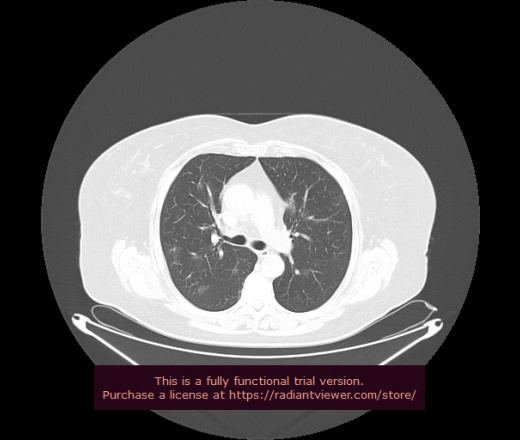

Уважаемые коллеги, если имеется интерес, сможете ли Вы спрогнозировать дальнейшее +-одинаковое течение процесса у 4 данных разных пациентов? Зацепиться где-то можно очень просто, где-то нельзя.